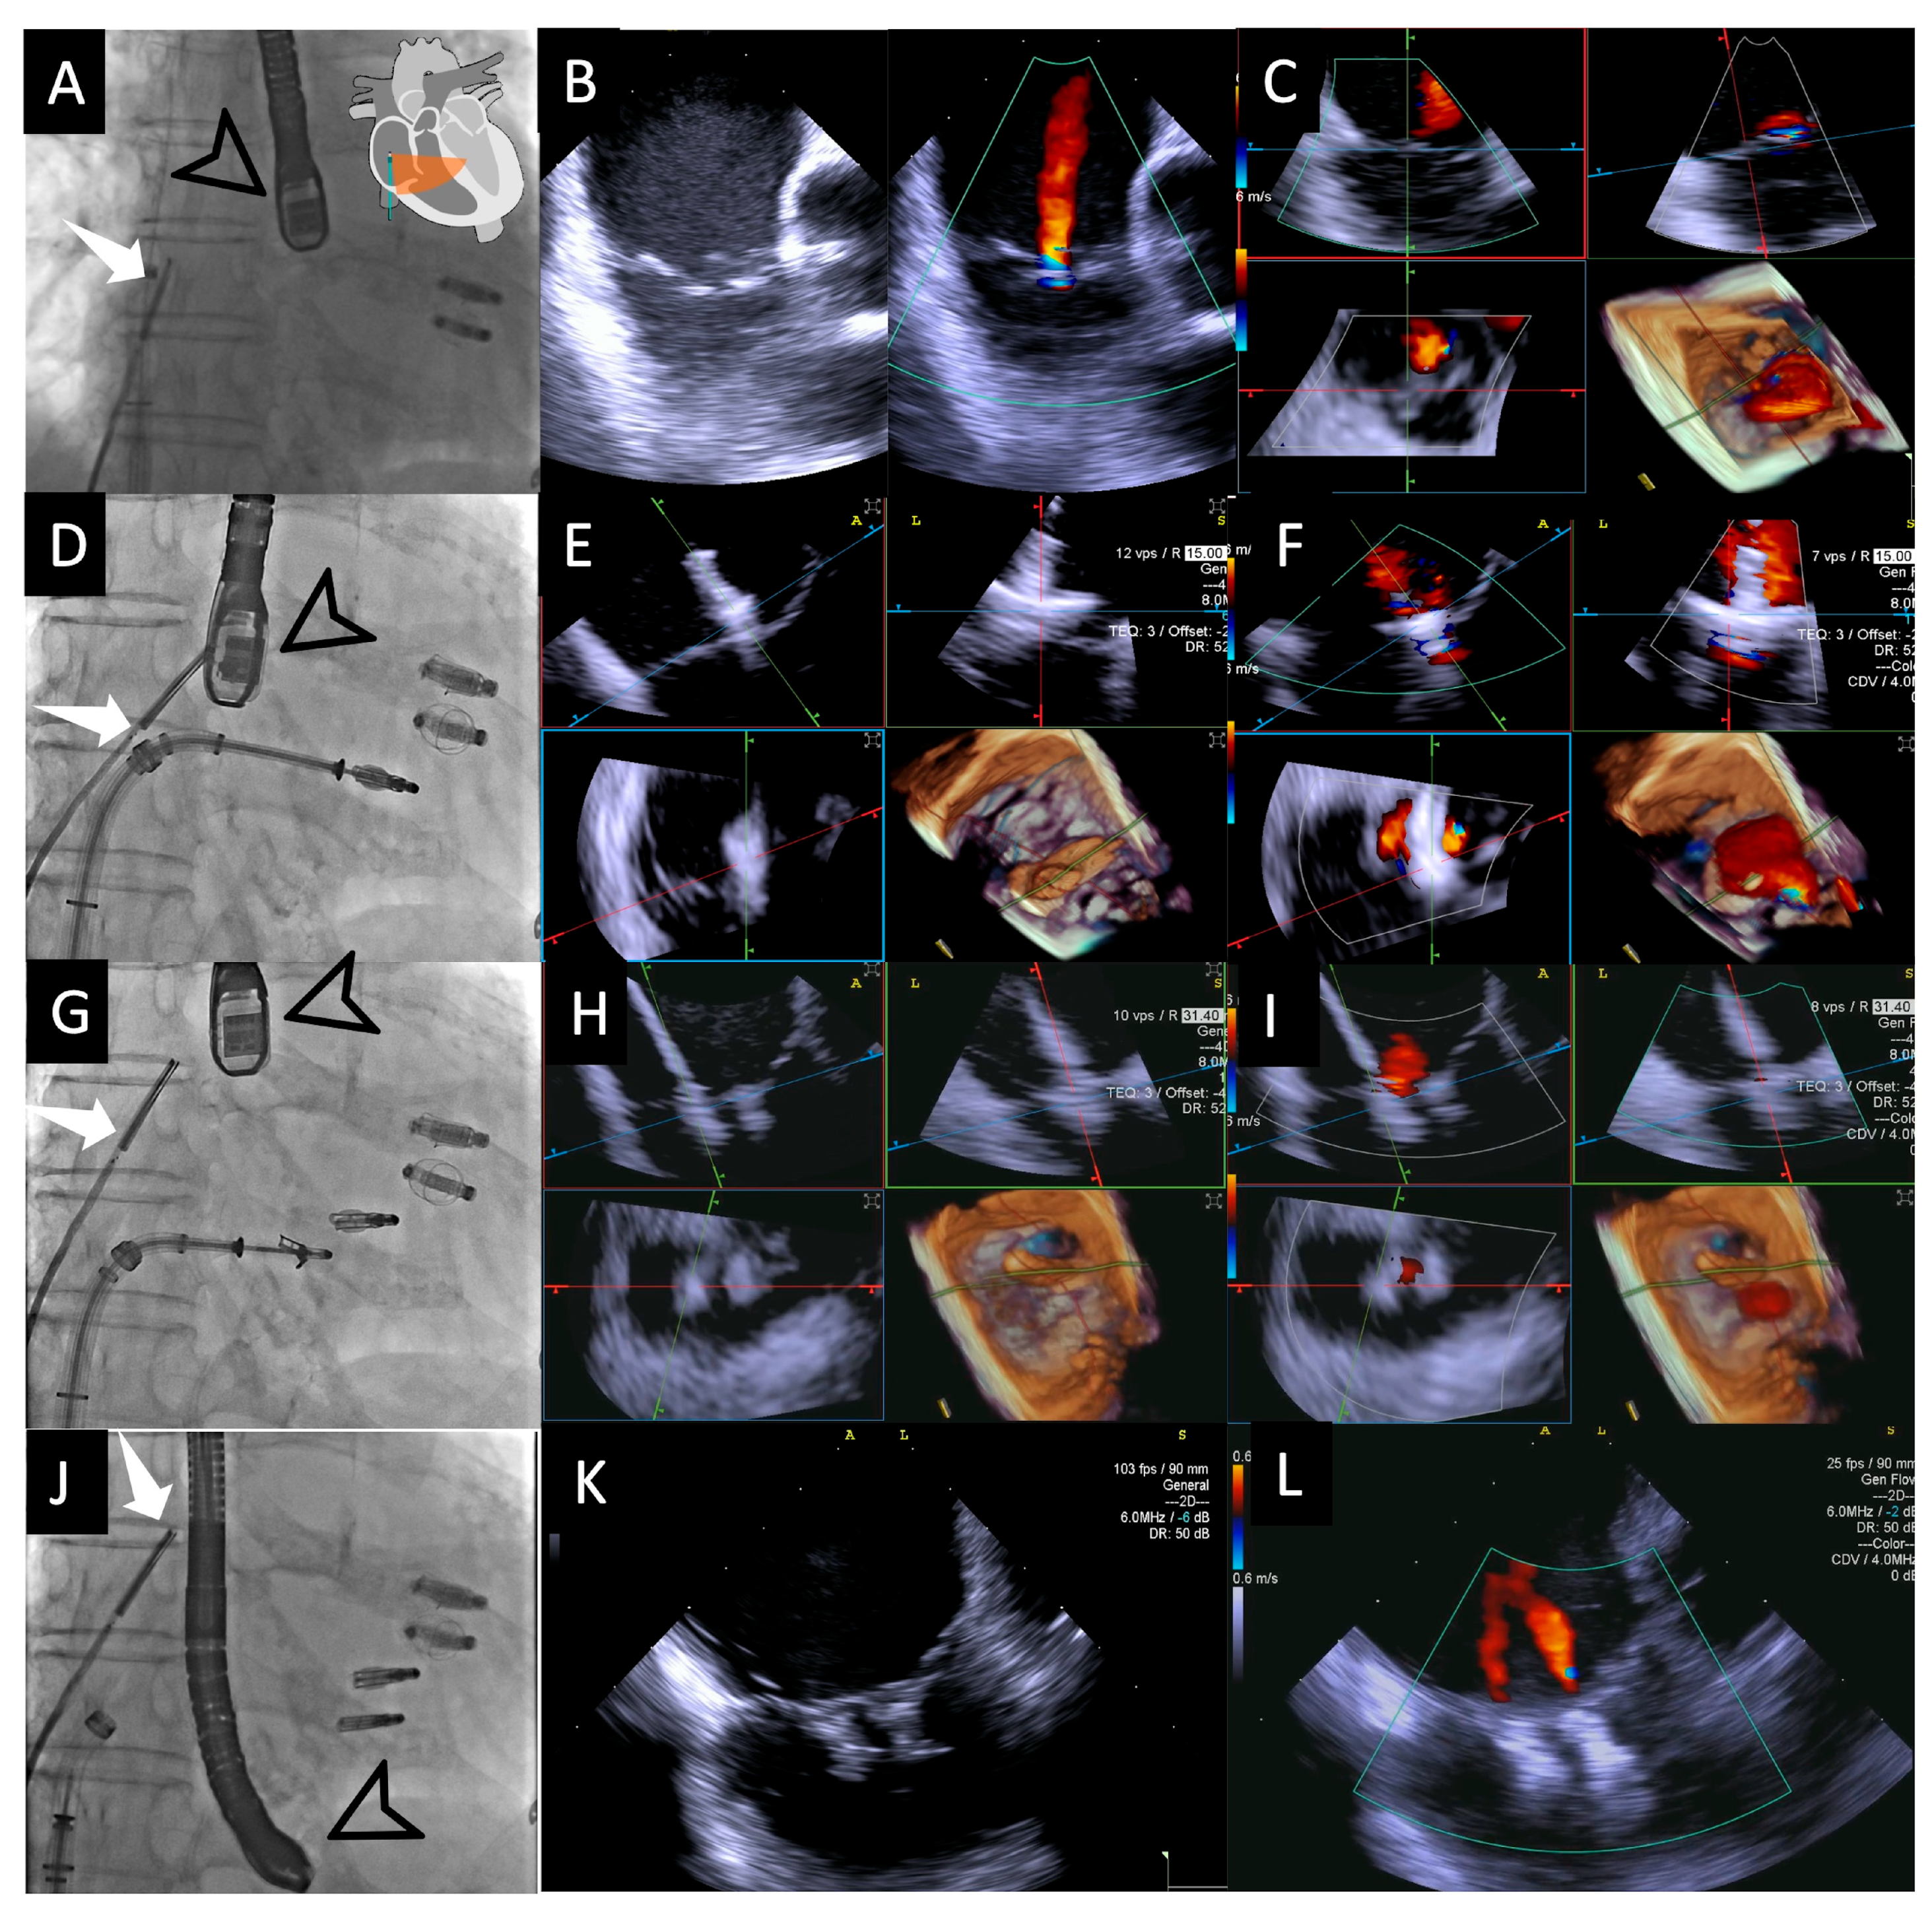

- Step number 3: steering and valve approach.

- Step number 4: ensuring perpendicularity and correct trajectory.

- Step number 5: clocking.

- Step number 6: grasping.

- Step number 7: leaflet insertion.

- Step number 8: evaluation of residual regurgitant jets.